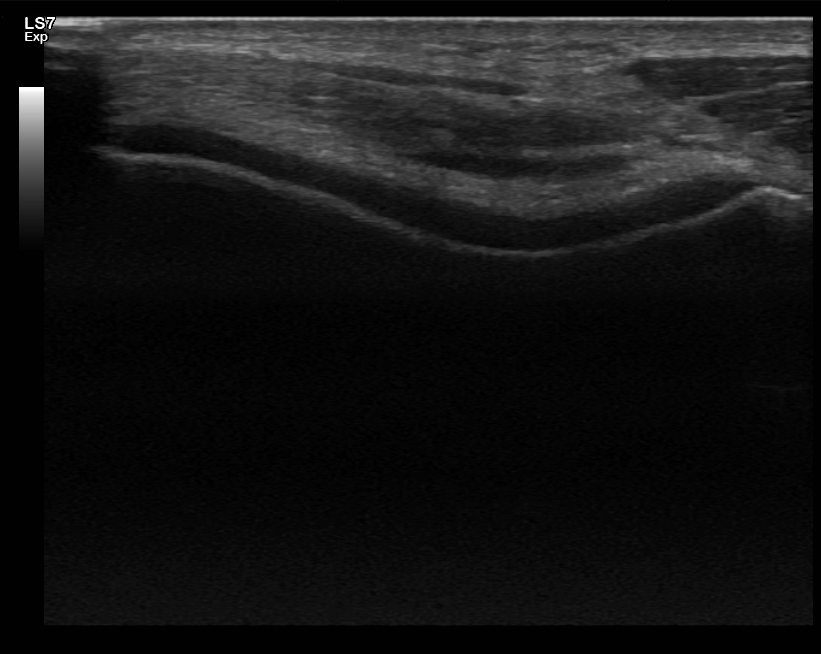

Polven ultraäänitutkimus

Polven ultraäänitutkimus on nopea ja turvallinen keino selvittää polven erilaisia oireita. Yleisimmät tutkimusaiheet ovat kipu – sekä liikkeessä että levossa – ja polven turvotus.

Polven nivelrikko on hyvin tavallinen, etenkin iän karttuessa. Ultraääni voi paljastaa nivelrikkomuutoksia jo ennen kuin ne näkyvät röntgenkuvissa. Samalla voidaan arvioida, onko polvessa ylimääräistä nestettä.